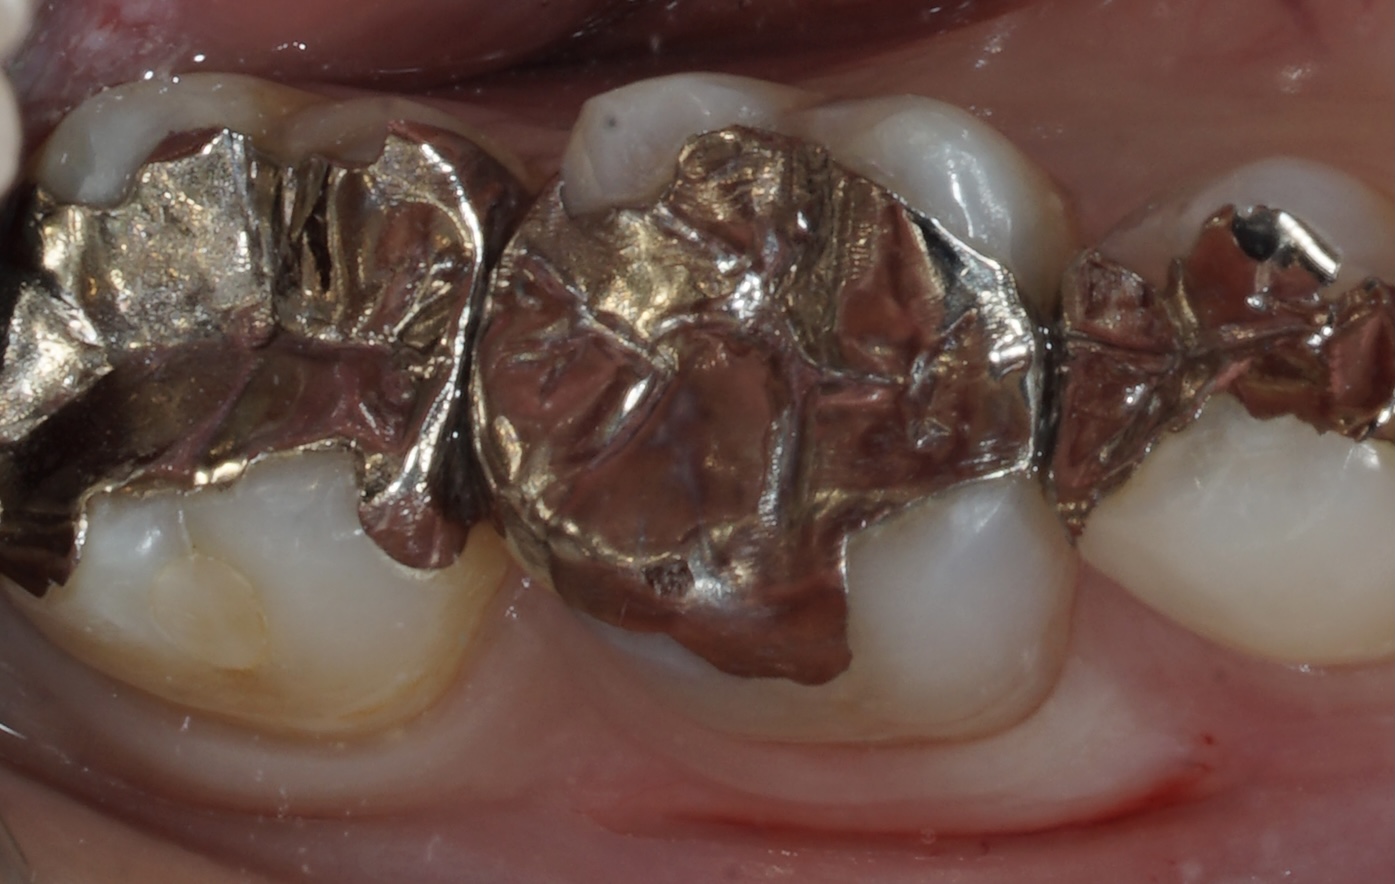

今回は前回の虫歯の都市伝説の続き、銀歯のリスクです。

みんな大嫌いな銀歯、目立つだけじゃないんですよ。

どんなリスクがあるのか見てみてください。

このような方、お気軽にご相談ください。ワイズは世間のイメージと違い

逆にお口が崩壊しているような

画像のような症例が得意です。